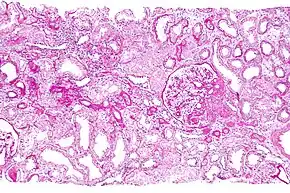

Micrograph showing a renal core biopsy. PAS stain.

Renal biopsy (also kidney biopsy) is a medical procedure in which a small piece of kidney is removed from the body for examination, usually under a microscope.[1] Microscopic examination of the tissue can provide information needed to diagnose, monitor or treat problems of the kidney.